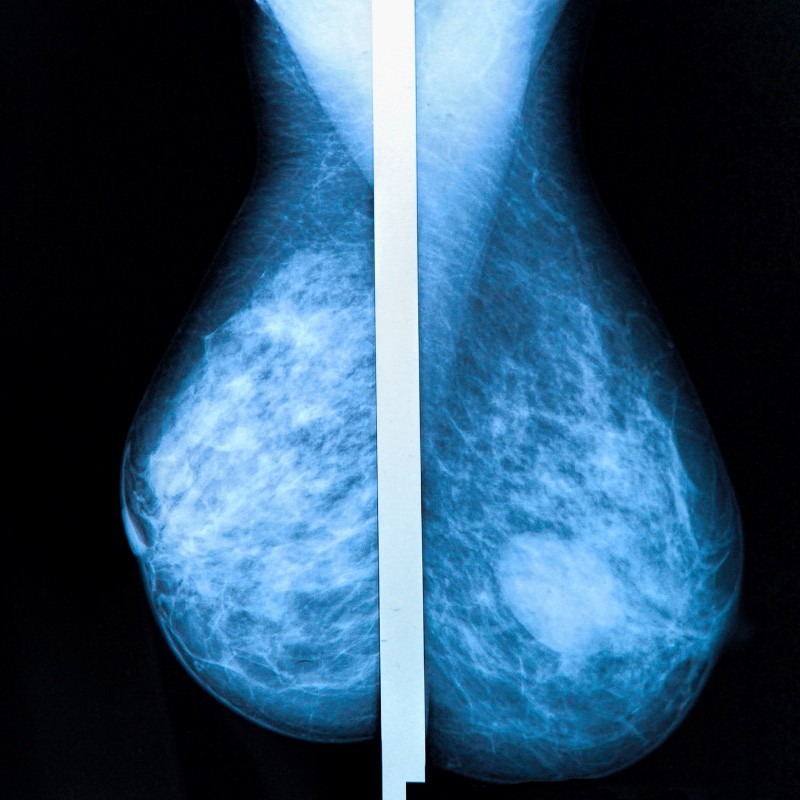

Con el propósito prevenir o, en su caso, detectar oportunamente el cáncer de mama, el Instituto Mexicano del Seguro Social (IMSS) en Veracruz Norte invita a las mujeres derechohabientes de 40 a 69 años, a acudir a la campaña de mastografías.

"Las mastografías buscan detectar cambios o anormalidades en los tejidos del seno que con el tiempo pueden dar problemas, si se descubre algún nódulo o masa, se deben realizar otros estudios para descartar o confirmar alguna otra patología", explicó la coordinadora auxiliar médico de Salud Pública, doctor José Artemio Cruz López.

Finalmente, Cruz López señaló que el horario de atención es de 08:00 a 18:00 horas y recomendó a las mujeres realizar este estudio, especialmente a quienes tienen más de 2 años sin llevarlo a cabo o nunca lo han hecho, ya que puede detectar nódulos o masas pequeñas, que son indetectables durante la autoexploración; una detección a tiempo, ¡salva tu vida!.